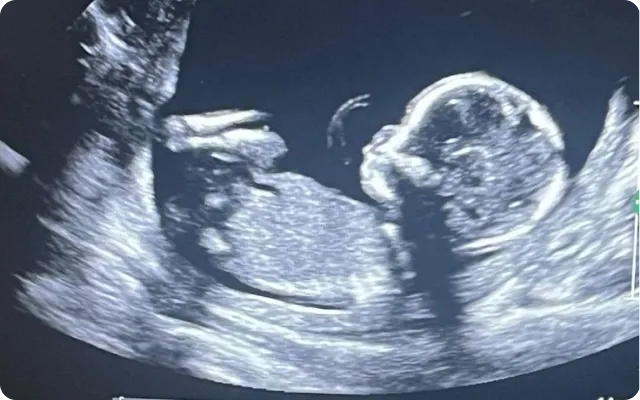

Fertility challenges can result from a variety of factors including ovarian reserve decline, endometrial lining concerns, hormonal imbalance, sperm quality issues, or unexplained infertility. Modern reproductive medicine often combines lifestyle optimization, hormonal management, and assisted reproductive techniques such as IVF when necessary.

Regenerative medicine approaches such as mesenchymal stem cell (MSC) therapy and platelet-rich plasma (PRP) are being explored for their potential role in supporting reproductive tissue environments, cellular signaling balance, and inflammatory regulation under medical supervision. These therapies are not designed to guarantee pregnancy or replace IVF treatment. Instead, they may be evaluated as complementary strategies aimed at supporting ovarian function, endometrial receptivity, or sperm environment quality as part of a personalized fertility plan.